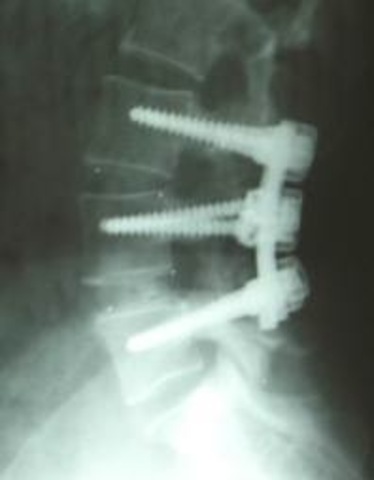

During 5th grade, I found out one of the disks in my lower back had slipped out of place and that I would need to fuse my bone back together. Because of this, my surgery was a week later. I now have two rods in my back and some nerve damage!